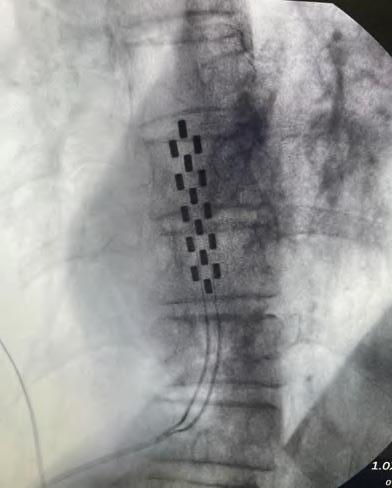

En enero de 2025, el equipo de columna de Clínica Bupa Santiago realizó una cirugía para el tratamiento de dolor crónico intratable, mediante la implantación de un estimulador medular de última generación. El procedimiento fue liderado por el Dr. Miguel Naranjo, traumatólogo especialista en columna, y marca un hito en el abordaje del dolor lumbar persistente, especialmente en pacientes que han agotado otras alternativas terapéuticas.

La paciente, con antecedentes de dolor lumbar crónico, había sido intervenida hace nueve años con una fijación y artrodesis de columna, sin lograr una resolución completa del dolor pese a múltiples tratamientos. Frente a este escenario, y tras una cuidadosa evaluación, se optó por implantar un estimulador medular como última alternativa terapéutica.

Tecnología avanzada al servicio de la calidad de vida

La cirugía consistió en la instalación de una placa de electrodos sobre la médula espinal, conectada a un generador que se ubicó en la zona abdominal. Este dispositivo emite impulsos eléctricos que bloquean la sensación de dolor antes de que llegue al cerebro, permitiendo una mejora significativa en la calidad de vida del paciente.

«El uso de esta tecnología ha demostrado una tasa de éxito cercana al 95%, siempre que exista una correcta selección de candidatos», explicó el Dr. Naranjo. «Hoy, gracias al trabajo de un equipo multidisciplinario y a los avances en diagnóstico, podemos ofrecer esta opción a pacientes que antes simplemente no tenían solución».